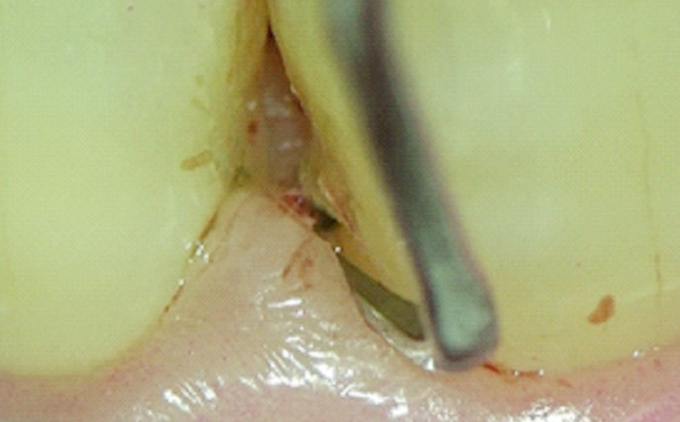

現代医療において、マイクロスコープは、脳外科、心臓外科、耳鼻科、眼科などの医科の分野では、あたり前のように使用されており、これは顕微鏡レベルでの拡大視野のもと行う施術の有効性を証明するものとして、疑う余地もありません。

歯科治療においても、顕微鏡下で行う根管治療(マイクロエンド)や、歯冠・歯根破折治療、顕微鏡下で手術を行うマイクロサージェリー、その他歯を削ったり詰め物をする際に、想像をはるかに超える威力を発揮します。

マイクロスコープで拡大することで、歯石の有無を確認し、過剰に組織にダメージを与える事を防げます。

歯周ポケットのような狭くて深い場所も、マイクロスコープで拡大すれば明示視野で行えるので、感染除去の確実性が格段に向上します。